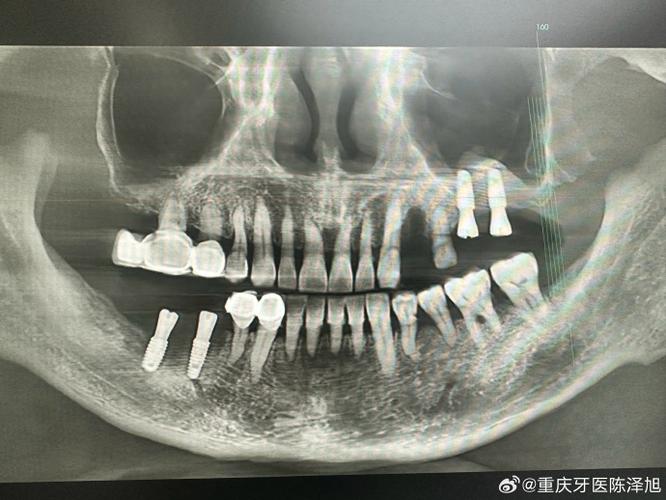

- 解决骨量不足: 牙齿缺失后,牙槽骨会逐渐吸收萎缩,导致骨头的高度、宽度或密度不足以安全、稳定地植入种植体,植骨就是通过移植骨组织(自体骨、异体骨、异种骨或人工骨)到缺损区域,增加骨量。

- 评估: 在等待期结束后,医生会通过临床检查和影像学检查(主要是CBCT)来评估新生骨的质量、高度、宽度是否达到了种植的要求。

- 二次评估: 拍CBCT检查骨愈合情况。

- 种植体植入: 如果骨条件成熟,即可进行种植手术,将种植体(人工牙根)植入新生骨中。